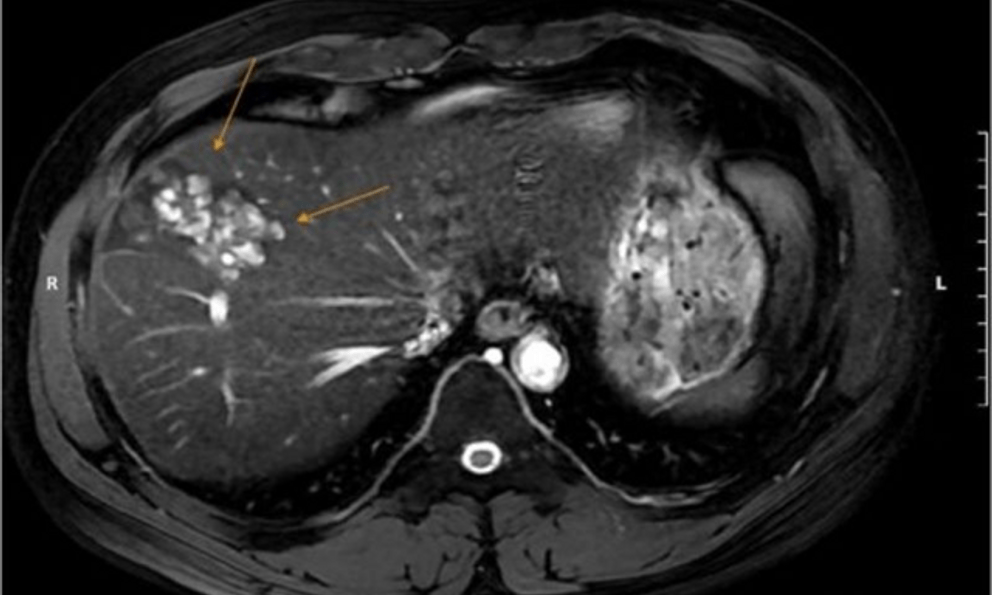

Để làm rõ chẩn đoán, bác sĩ chỉ định anh N. chụp cộng hưởng từ (MRI) ổ bụng, kết quả phát hiện nhiều ổ tổn thương khu trú gan phải, dạng hoại tử dịch hóa nhiều ổ, nghi ngờ do ký sinh trùng. Đồng thời, xét nghiệm chuyên sâu xác nhận dương tính với sán lá gan lớn và giun lươn.